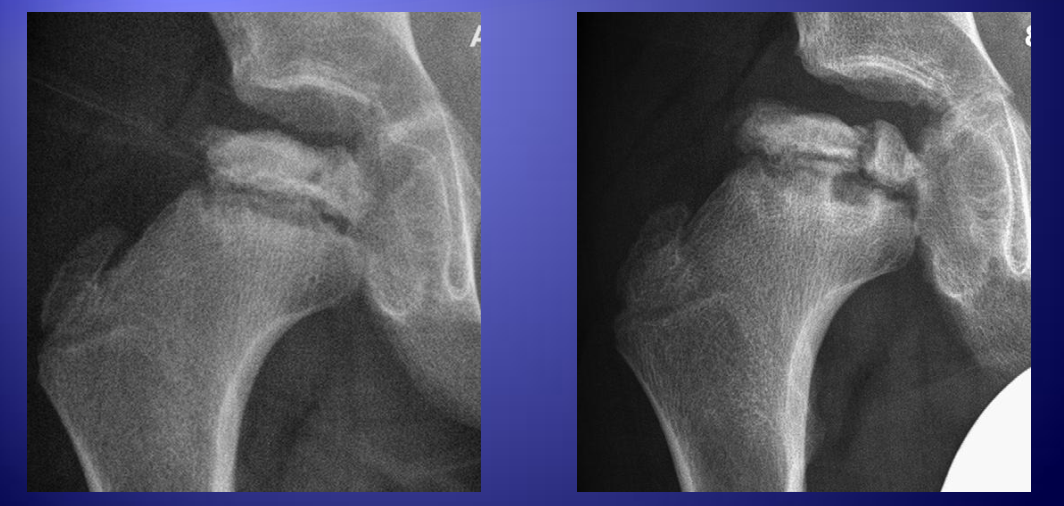

辅助检查: 全血细胞计数、C 反应蛋白、红细胞沉降率可以鉴别化脓性髋关节炎。一过性髋关节滑膜炎在此年龄段的儿童也较为常见。持续跛行的患儿应于 8~12 周后重复拍 X 光片,以鉴别滑膜炎。 大多数情况下,骨盆正位加双髋关节蛙式位 X 光片足以证实诊断。个别处于疾病早期的患儿 X 光片显示正常。特征性影像学表现先后出现于:股骨骺、干骺端、髋臼。Perthes 病的 X 光片表现分为四期,每期持续数月。1 期:股骨骺硬化;2 期:股骨头受压变形;3 期:再生期;4 期:修复期。